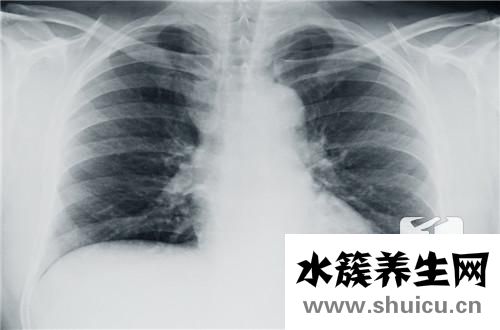

眾所周知,生活在胸腔里的人體最重要的器官是人的心臟。一旦人類心臟出現問題,就沒有心臟移植等外科治療。所以,保養心臟很重要。患有心腦血管疾病的人經常感到胸部不舒服。這時候他們會去醫院做胸透...